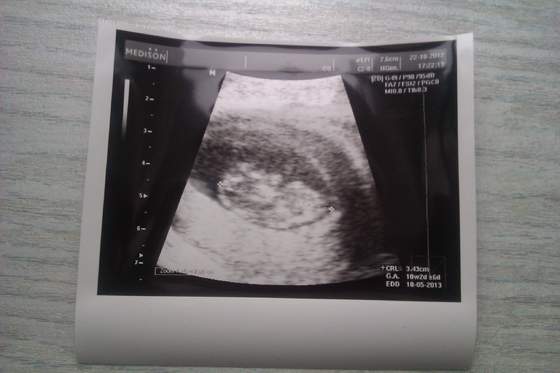

A ja dołączam zdjęcie

Załączniki

• usg 9w6d.jpg

usg 9w6d.jpg

19,2 KB · Wyświetleń: 102